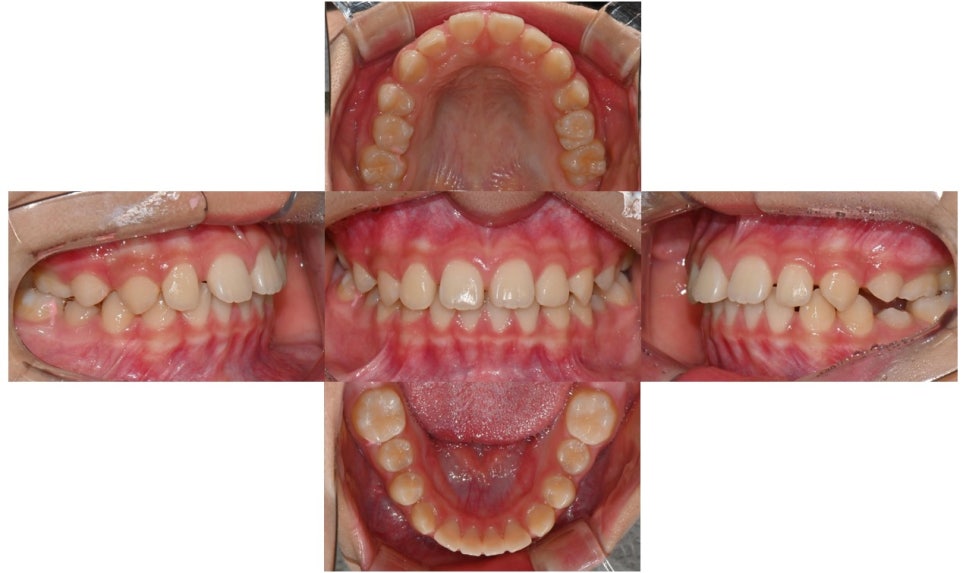

약 9개월간 2급 액티베이터와 헤드기어 착용 후 모습입니다.

2025.5.16.

어금니 관계의 위치변화

치료 결과 하악골은 전방성장하였으며, 과개교합도 많이 개선되었습니다. 헤드기어로 상악골의 성장도 억제되어 돌출되었던 위 앞니 각도도 개선되었고, 위-아래 앞니 사이 간격이 많이 줄었습니다. 위 앞니에 눌려 돌출되었던 하순도 개선되어 straight profile이 완성되었습니다.

환자가 올해 말 출국 계획이 있어서 인비절라인 퍼스트로 최대한 출국 전까지 남아있는 치아 사이 공간을 닫기로 하였습니다. 장치는 총 20단계로 출국 전 마무리를 목표로 장치 착용 중입니다. 영구치가 모두 맹출한 이후 추가적인 교정이 필요할 경우, 방학 때 한국에 들어올 때 워런티 기간 내에 추가교정장치로 마무리해드릴 예정입니다.